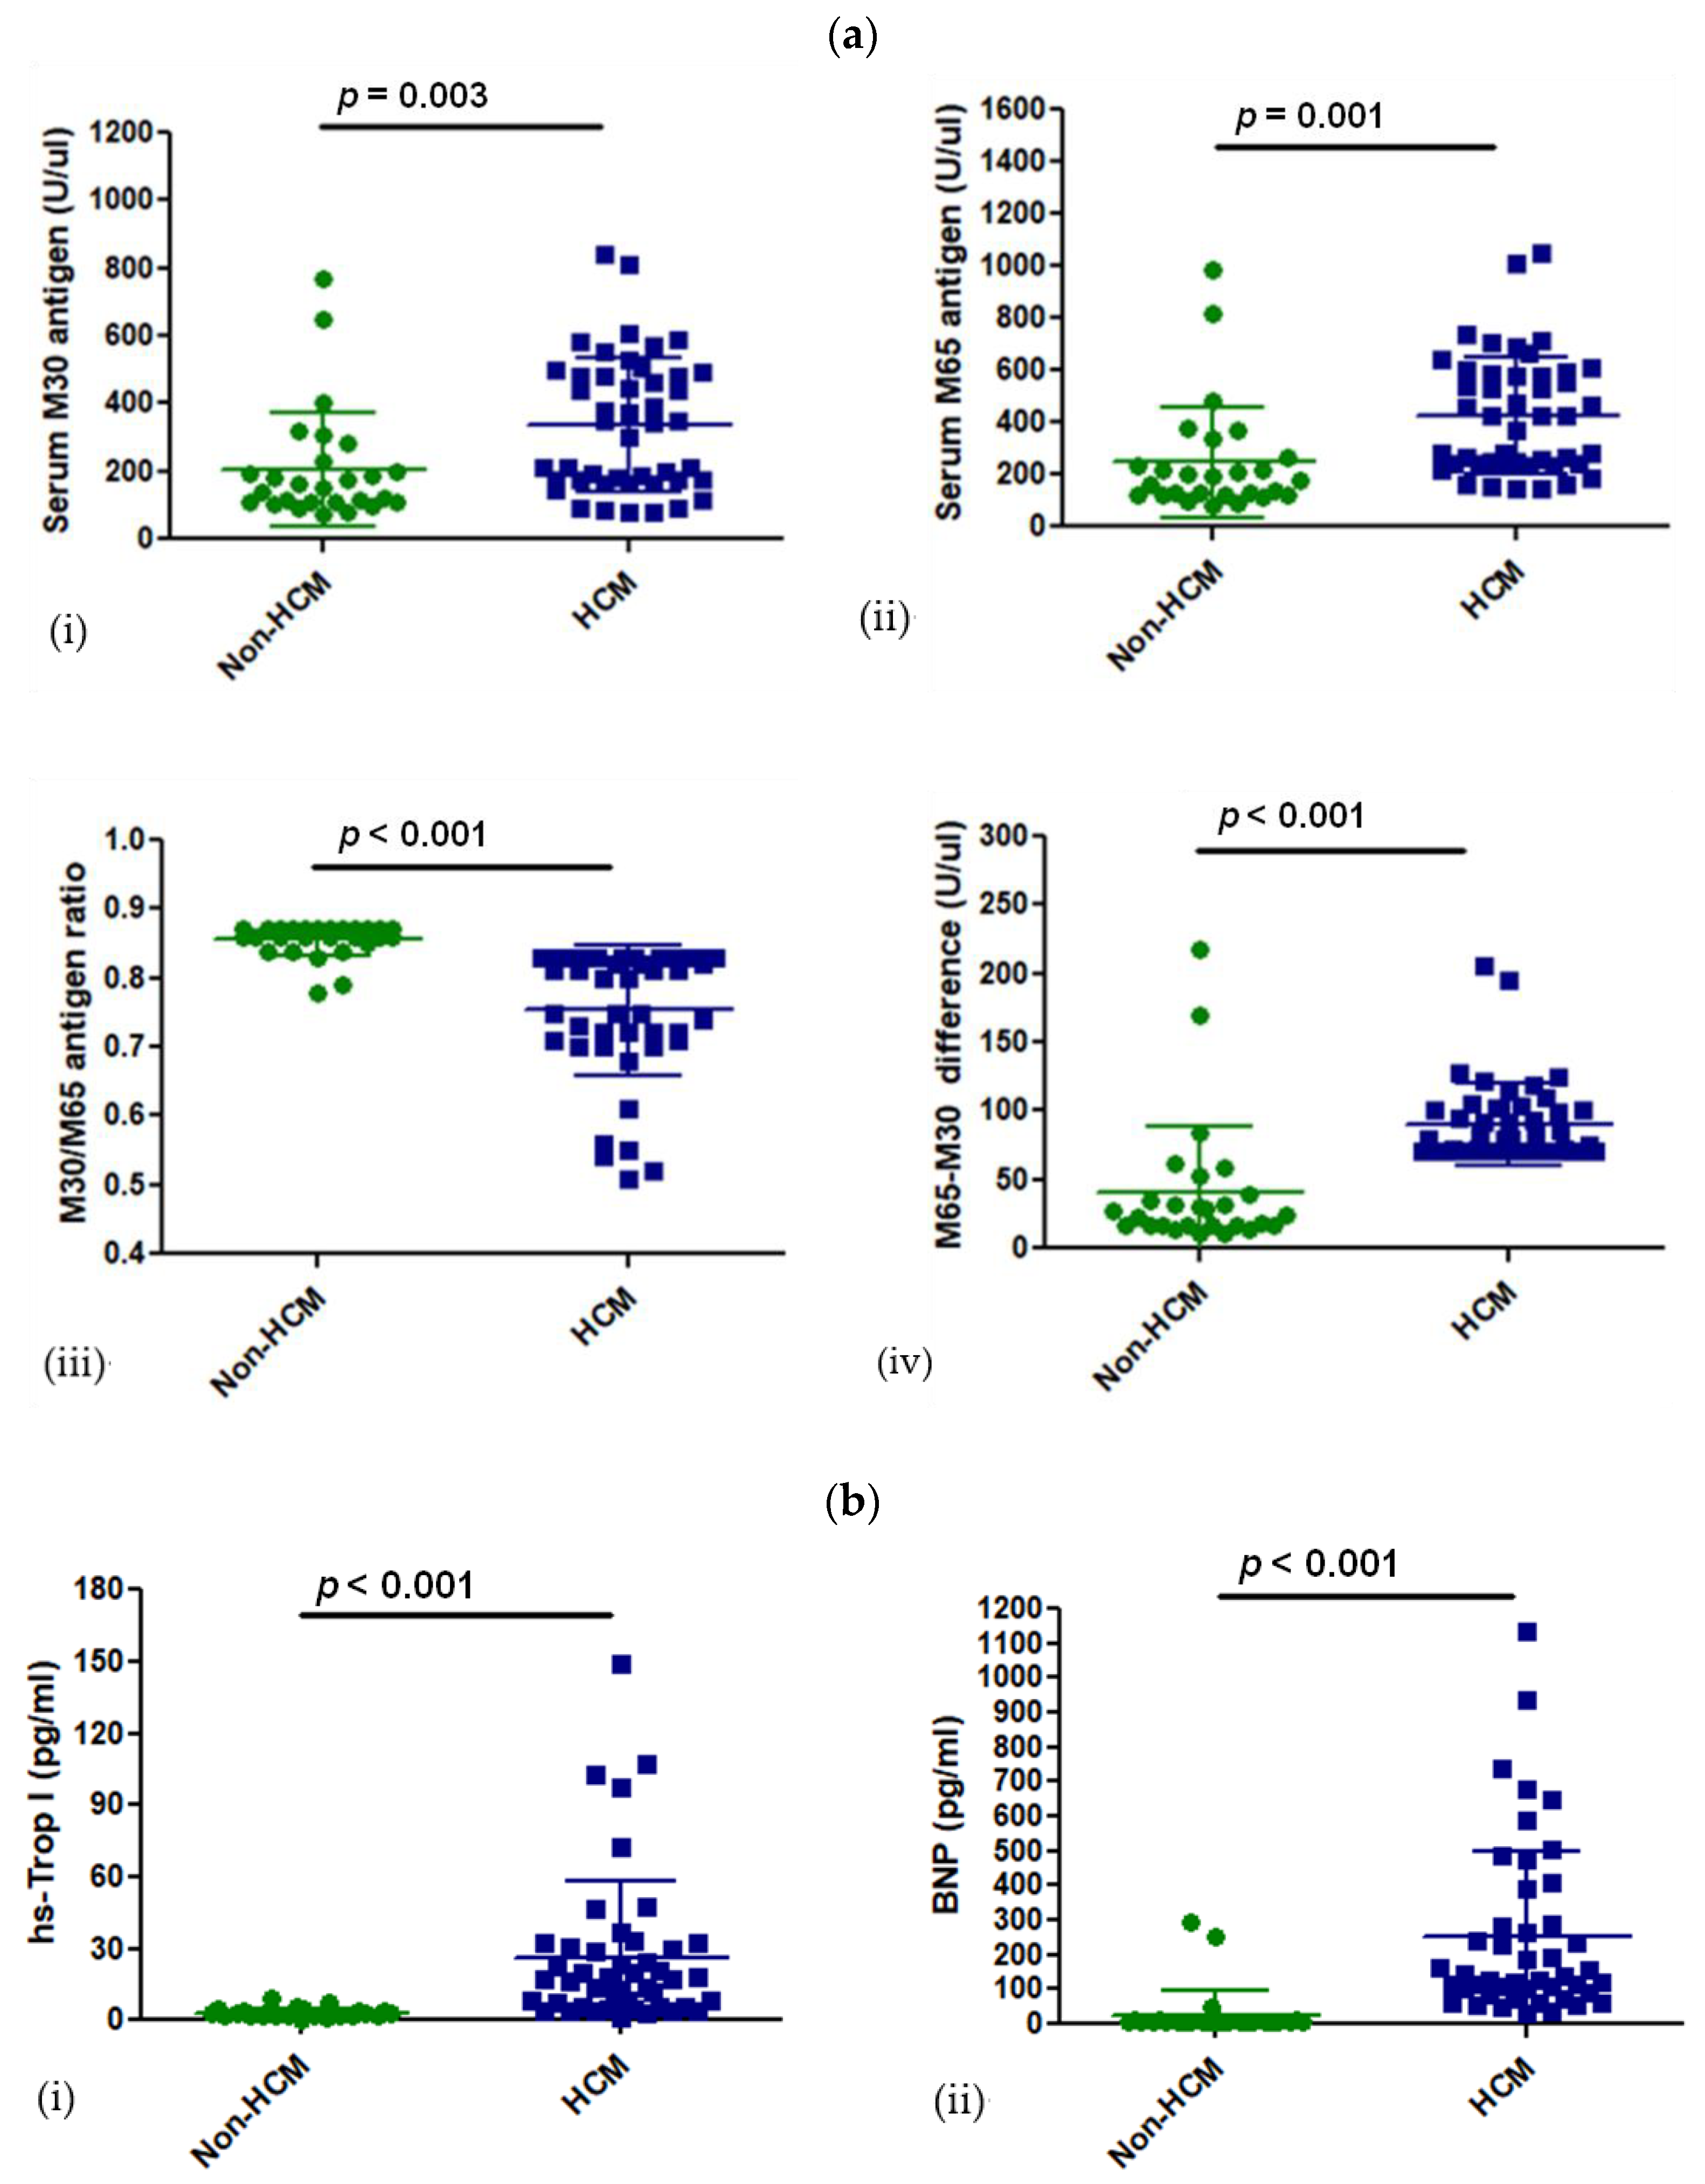

3.2. Levels of CK18 and Its Caspase-Cleaved Product in the Blood Serum of Patients with HCM

3.3. M30 and M65 Expression in HCM Group with or without High Risk for SCD